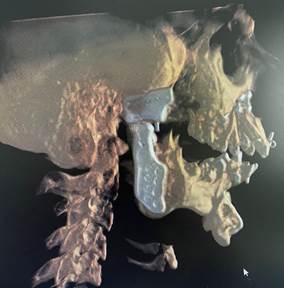

The second step is conversion of the imaging data into three dimensional digital models of the face.

Once the 3D reconstructed models are obtained, the surgeon and the engineers simulate the surgical steps on the model. The ankylotic mass is removed and the prosthetic components are positioned digitally in the desired position replicating normal anatomy.

Based on the virtual surgical planning, the patient-specific implants are customised. Along with these implants, surgical guides are fabricated to aid in surgical precision and improved surgical time.